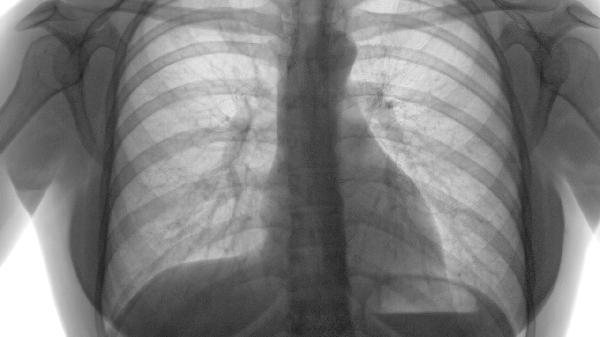

肺活量大有助于提升心肺功能、增强身体耐力和免疫力,对整体健康有显著益处。肺活量是指一次最大吸气后尽力呼出的气体总量,与呼吸系统、心血管系统以及身体代谢密切相关。通过锻炼、调整呼吸方式和改善生活习惯,可以有效提高肺活量。

1.提升心肺功能。肺活量直接影响心脏和肺部的供氧能力。较大的肺活量意味着肺部能够吸入更多氧气,并通过血液循环将氧气输送到全身各器官,从而提高心脏的工作效率。长期保持较高的肺活量,可以降低心血管疾病的风险,如高血压、冠心病等。建议通过有氧运动如跑步、游泳、骑自行车等来增强心肺功能。

3.提高免疫力。肺活量与呼吸系统的健康密切相关,较大的肺活量有助于清除肺部有害物质,减少呼吸道感染的风险。同时,充足的氧气供应可以促进免疫细胞的活性,增强身体对病毒和细菌的防御能力。日常生活中,可以通过戒烟、避免空气污染、保持室内空气流通等方式保护肺部健康。